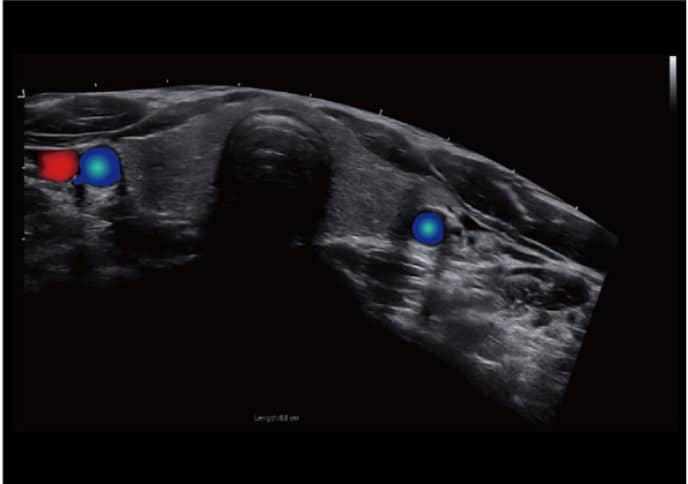

– Nó có khả năng chụp ảnh đa phương thức cùng với nhiều chức năng tự động như SonoColor , SonoCrystal , SonoAI-OB, Intelligent doppler, Sonocontrast , SonoNeedle , Color toàn cảnh , Dữ liệu thô …

- Doppler Thông Minh: Tự động điều chỉnh hướng ROI và PFR, đem lại hiệu quả và dễ dàng đo lường hơn, tập trung vào bệnh nhân một cách tối ưu.

CBit 9 được trang bị với đa dạng các loại đầu dò như Linear, Convex, Khối, Âm đạo, Tim, Micro-Convex, giúp đáp ứng mọi nhu cầu khám chữa bệnh của người dùng.